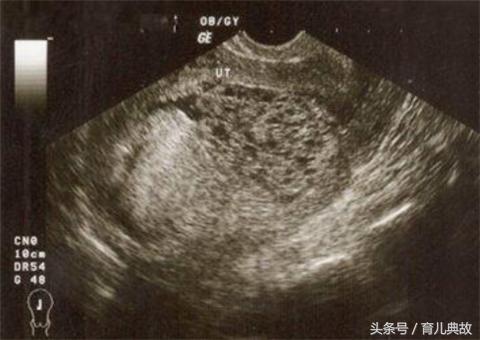

5、怀的是葡萄胎时,在B超下看不到正常胎儿的形态,而是出现雪片状或蜂窝状的图片。